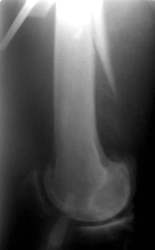

Diese Fraktur ereignete sich 8 Wochen nach Prothesenwechsel. Der Wechsel war bereits problematisch, Frakturen wurden mit Drahtcerclagen befestigt. Es handelte sich jetzt um eine Stückfraktur.